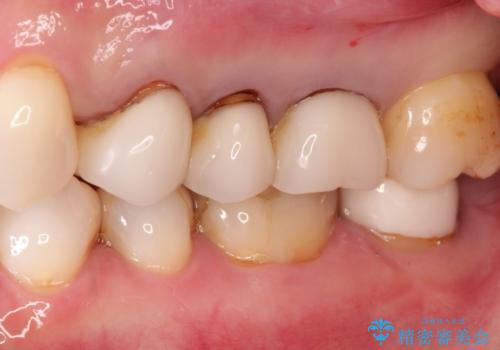

強度に優れたオールセラミッククラウンにて治療を行なっております。

3歯同時に治療を行うこと来院回数は4回で終了しています。

セラミック治療の注意事項(リスク・副作用など)